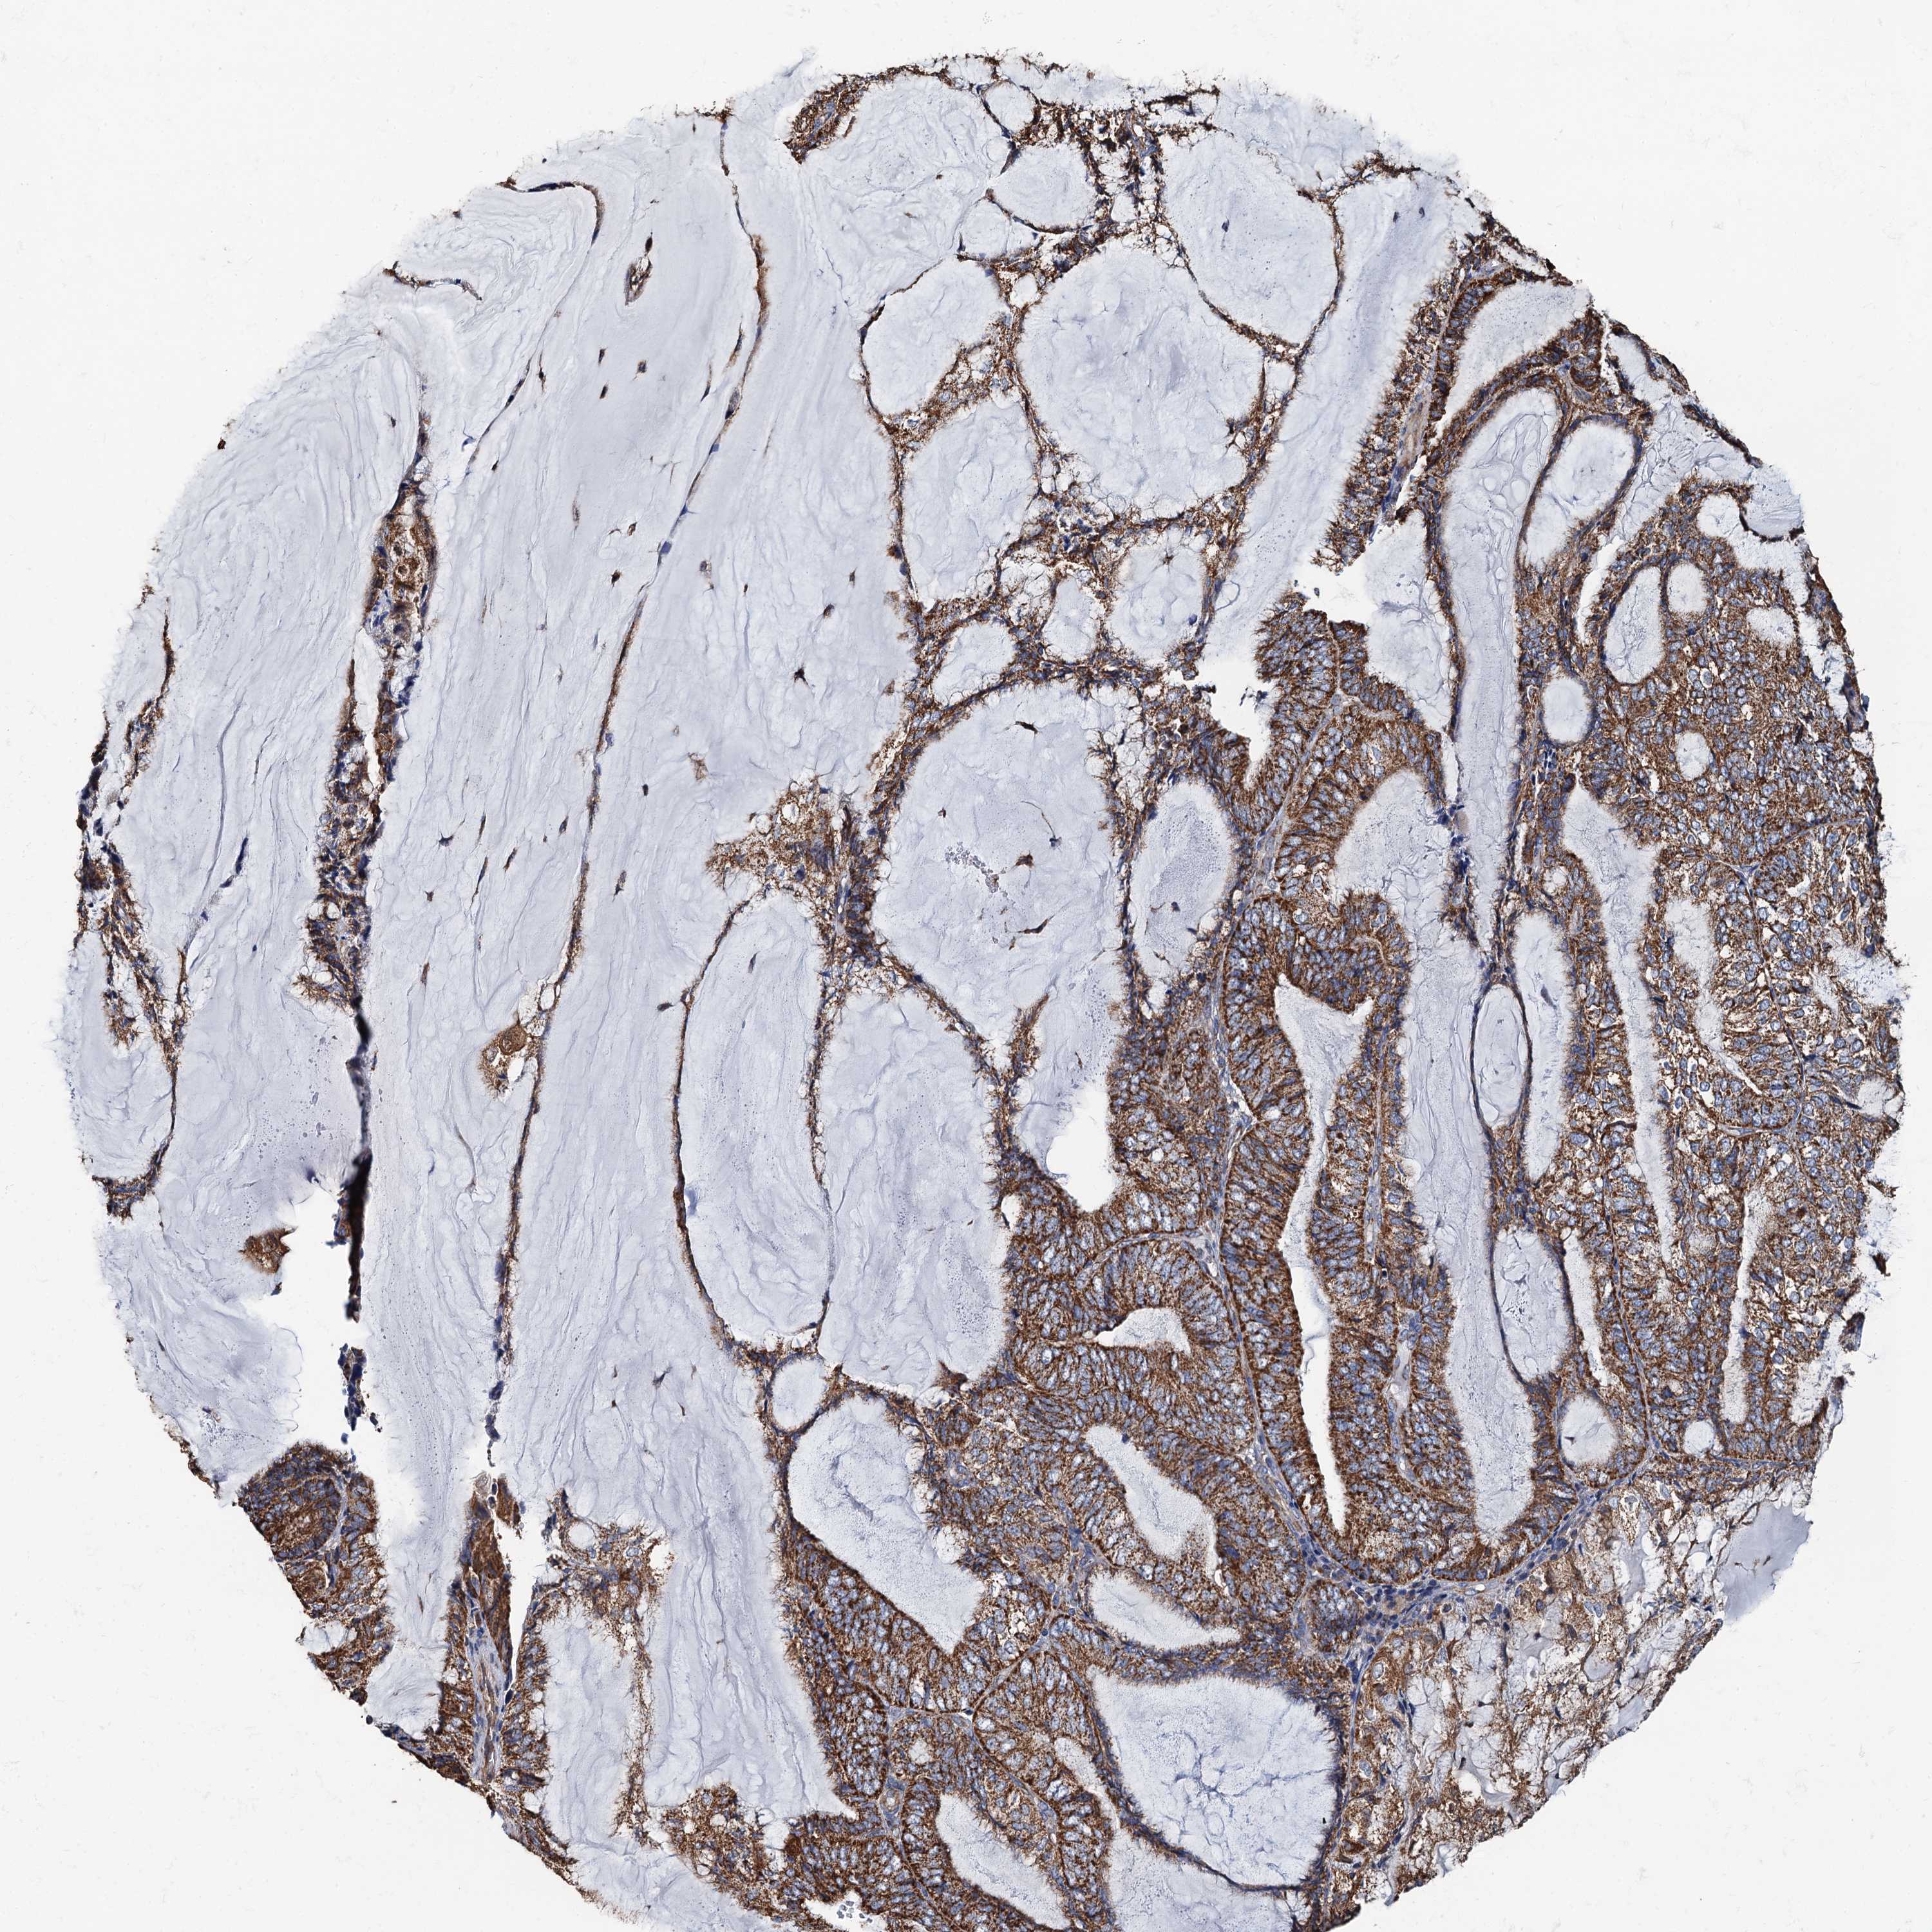

ENDOMETRIAL CANCER - Protein expressioni

A mouse-over function shows sample information and annotation data. Click on an image to view it in a full screen mode. Samples can be filtered based on level of antibody staining by selecting one or several of the following categories: high, medium, low and not detected. The assay and annotation is described here.

Note that samples used for immunohistochemistry by the Human Protein Atlas do not correspond to samples in the TCGA dataset.

Antibody stainingi

Antibody staining in the annotated cell types in the current human tissue is reported as not detected, low, medium, or high, based on conventional immunohistochemistry profiling in selected tissues. This score is based on the combination of the staining intensity and fraction of stained cells.

Each image is clickable and will lead to virtual microscopy that enables deeper exploration of all samples and also displays staining intensity scores, fraction scores and subcellular localization as well as patient and tissue information for each sample.

Antibody HPA039371

Antibody HPA040174

Staining

High

Medium

Low

Not detected

Intensity

Strong

Moderate

Weak

Negative

Quantity

>75%

75%-25%

<25%

None

Location

Nuclear

Cytoplasmic/membranous

Cytoplasmic/membranous,nuclear

Adenocarcinoma, NOS